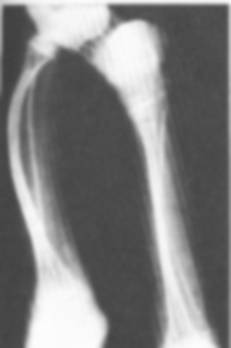

7. Osteogeneza imperfecta (congenitala Vrolick, tardiva Lobstein)

- este o enzimopatie complexa care determina o insuficienta periostala congenitala;

- clinic: sclere albastre, otoscleroza, nanism dizarmonic;

- radiologic: os transparent ca de sticla si hipoplazic, craniu cu bordura, hiperlaxitate ligamentara, fracturi patologice, deformari osoase si nanism secundar.

Fig. 116 - Osteogeneza imperfecta tardiva Lobstein